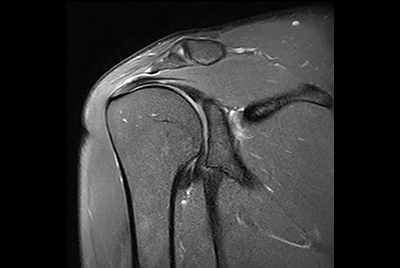

Push-button Shoulder exam, under 5 minutes

Routine shoulder imaging

High resolution shoulder imaging

Shoulder with the dS Shoulder 16ch coil

Shoulder imaging